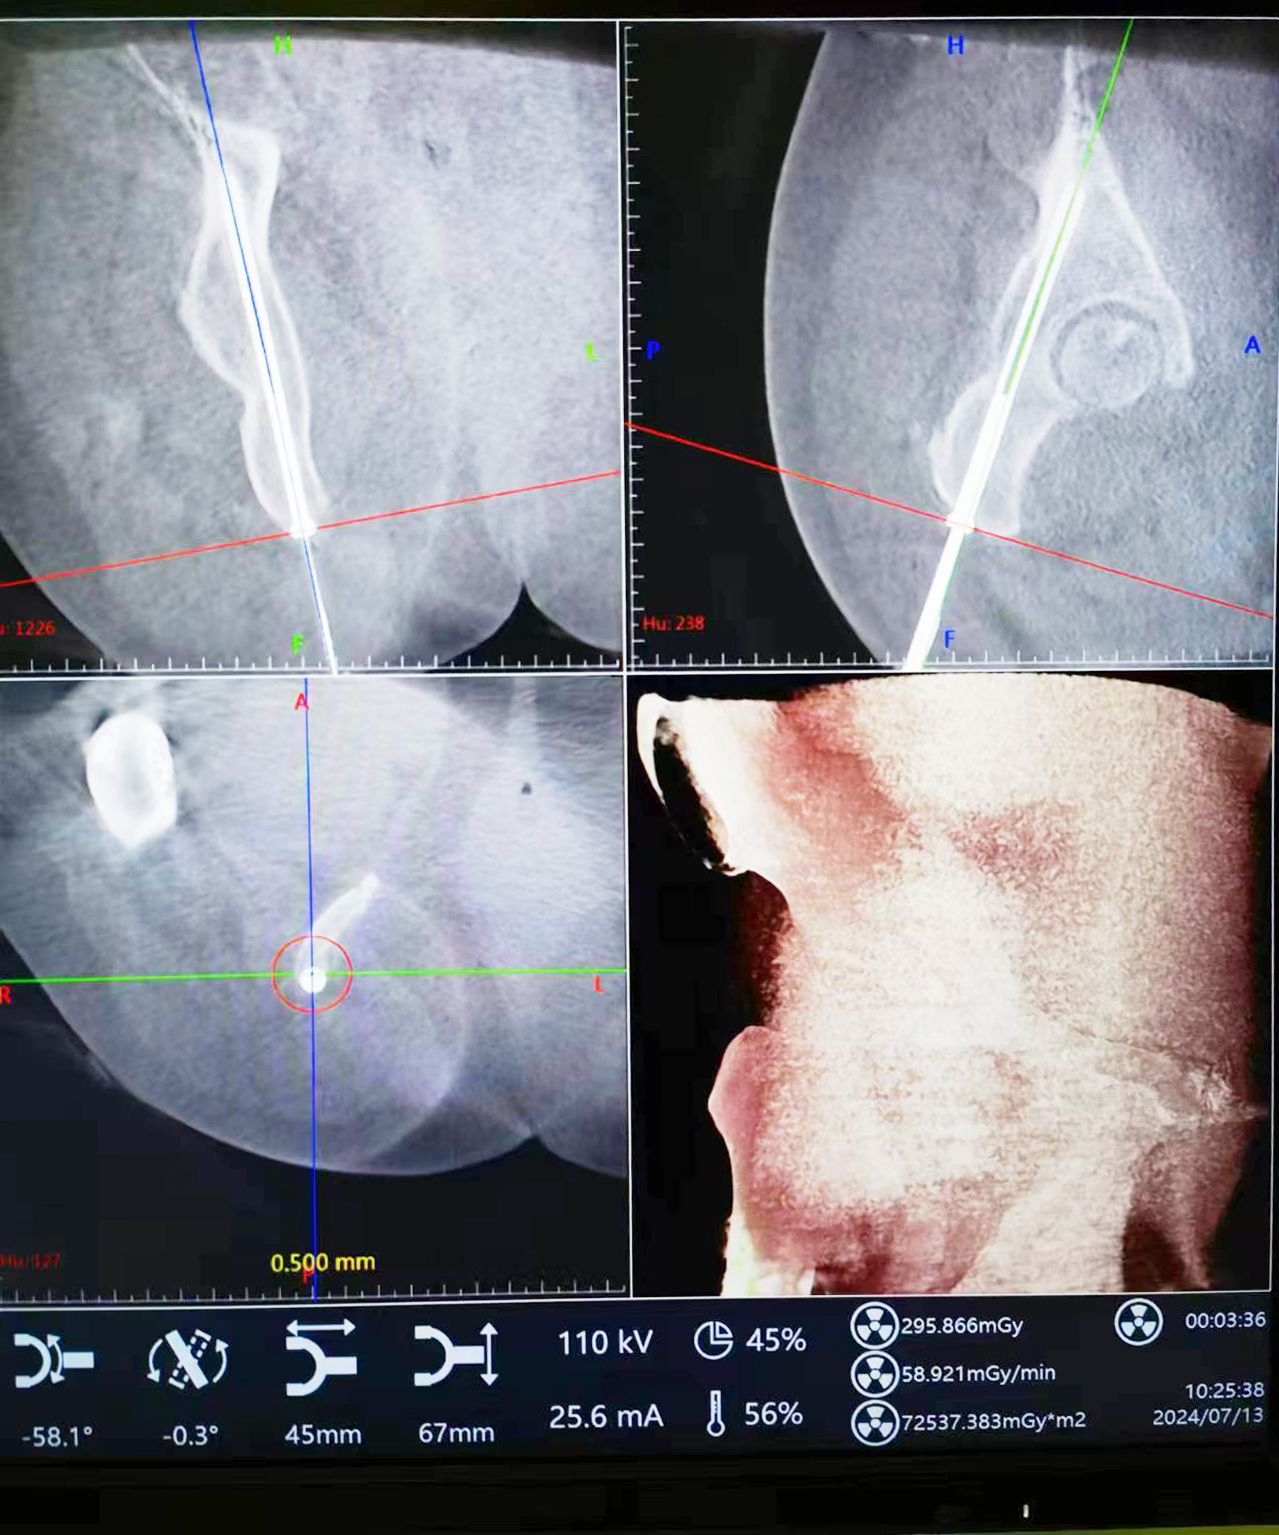

患者,女,50歲,因“車禍傷致右髖部疼痛伴活動受限2h”收住院,診斷為“右側(cè)髖臼后柱骨折”。入院后,劉志主任及宋遠征主治醫(yī)師綜合評估患者病情及骨折類型后,決定給予患者行“機器人導航輔助下微創(chuàng)經(jīng)皮后柱通道螺釘內(nèi)固定術(shù)”。

術(shù)中將示蹤器用克氏針固定于患側(cè)髂后上棘,將采集到的圖像傳輸至主控臺用于對骨盆通道螺釘進行路徑規(guī)劃,選擇螺釘直徑、長度、入點、止點。在遙控導航下,機器人將機械臂沿著規(guī)劃路徑移動到目標位置,置入導針和螺釘。術(shù)中驗證髖臼后柱螺釘置入位置精準,切口1.0cm。